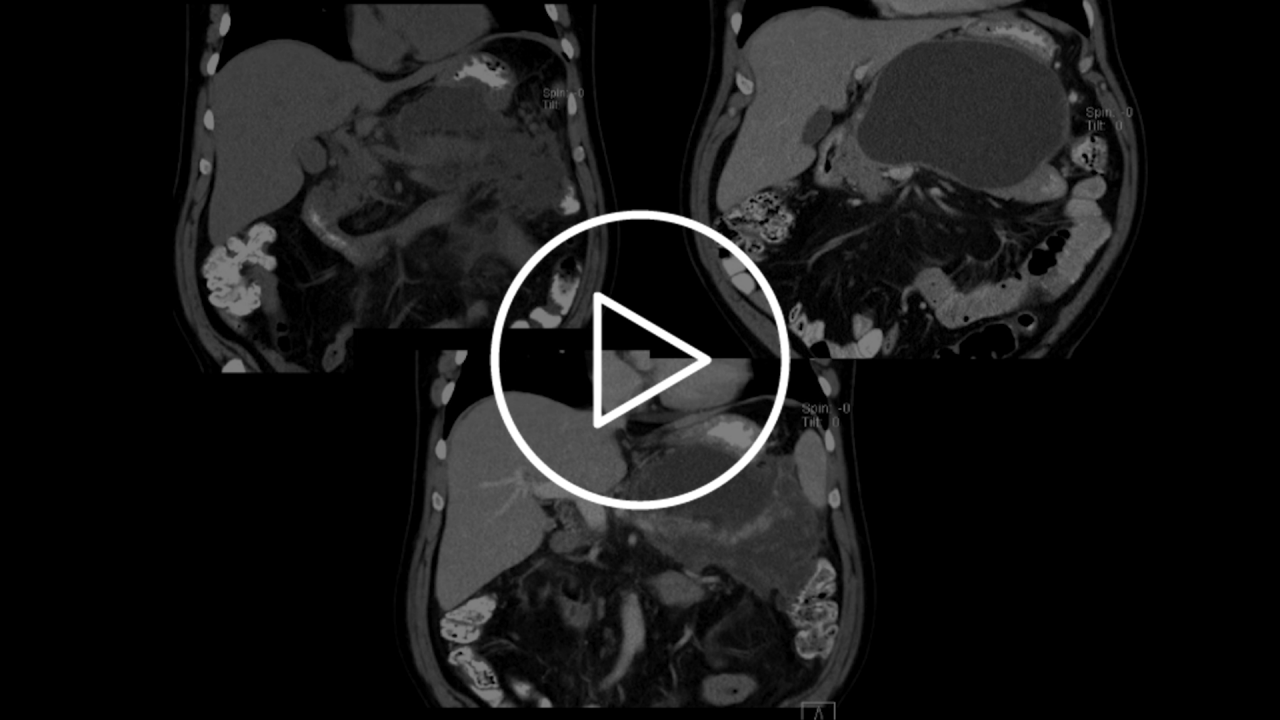

The training is a field-led educational experience for physicians who have completed the Hot AXIOS training and want to increase their confidence. This training will be organized in your hospital with a review of Hot AXIOS indications and a practical hands-on session.

Ask your sales representative about the opportunity to organize training session in your facility.

The training session inlcudes lecture and hands-on where you deploy at least 5 Hot AXIOS within a synthetic model.

Deep dive into EDUCARE recommended resources and take advantage of e-proctorship through the ExpertLink remote connectivity solution.